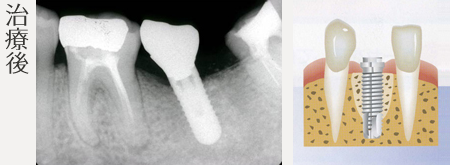

骨幅、高さを回復したおかげで インプラント治療が可能です。

治療内容

- 骨造成(1歯)

- インプラント(1本)

- インプラント上部金合金前装冠 (1本)